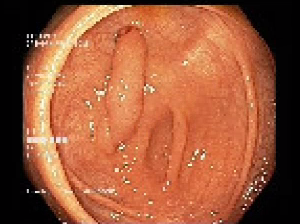

The colonoscopy was inserted to the terminal ileum. An inverted appendix measuring 30mm was visualised in the caecum (Figures 1&2). No obvious lesion was seen on the mucosal surface of the appendix. No signs of small bowel or colonic intussusception was evident. The colonoscopy was otherwise unremarkable, except for some small second degree haemorrhoids (Figure 3) No biopsy was taken. Patient was well post colonoscopy.